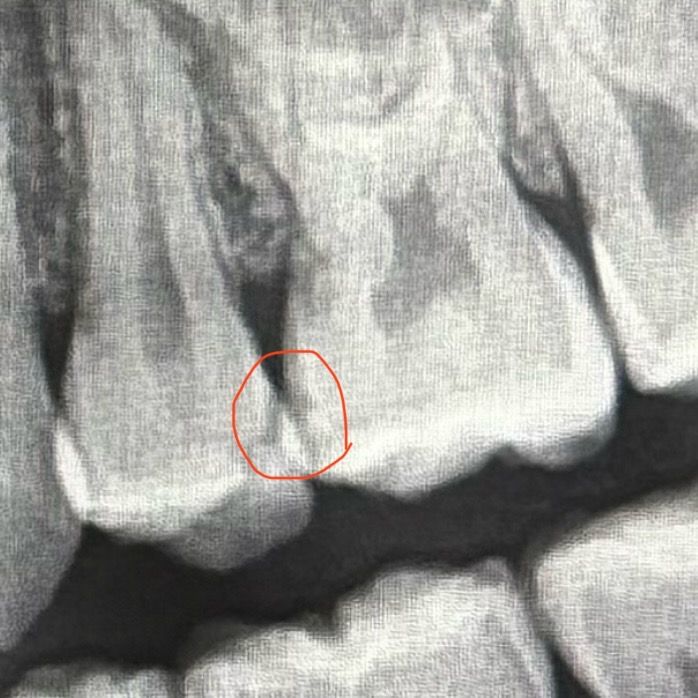

레진 치료 한 부위인데 이거 충치인가요?

제가 인접면 레진치료를 했는데 타병원 가니까 충치라면서 인레이 하자고 하거든요.... 정말인가요..?ㅠㅠ

인접면이고 또 엑스레이상에서 저렇게 거뭇하게 나오니까

사진상으로 검게 보이는 부분은 보통 치질이 약하거나 석회화가 약해진 부분입니다. 인접면에 충치가 생겼을 가능성이 있습니다. 이런 경우 범위를 더 크게 해서 치료를 해야 할 수 있습니다.

1. 레진하방으로 이차충치가 있을 것으로 엑스레이상 추측이 되긴 합니다.

2. 다만, 아주 100% 확실하진 않습니다. 실제 임상 증상은 어떤지도 확인하고 눈으로 봐야하는 부분도 있습니다.